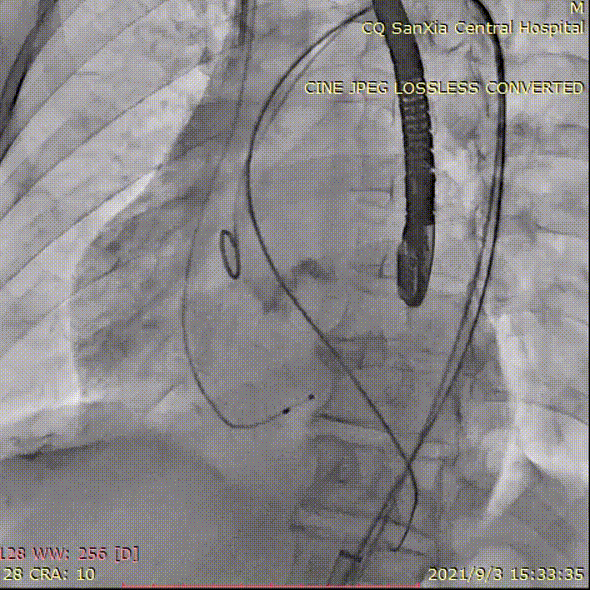

置入lunderquist

植入L23瓣膜定位,进行高位释放